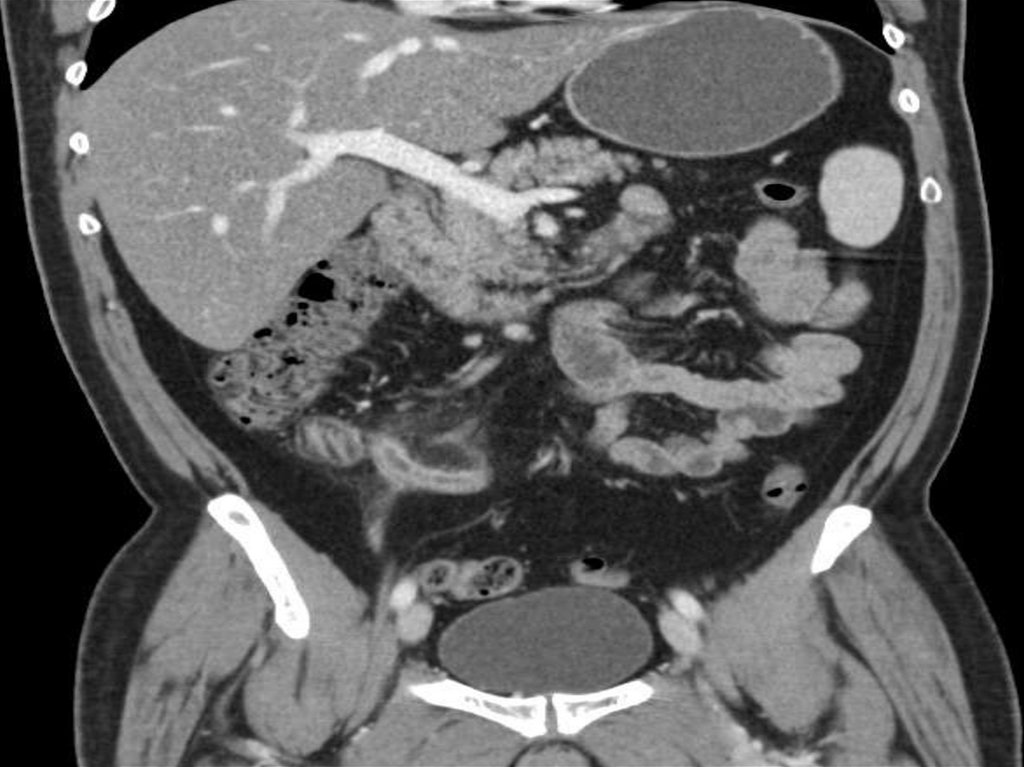

• Живот и таз:

1. Травмы живота и таза;

2. Исследование паренхиматозных органов

пищеварительной системы (печень, поджелудочная

железа);

3. Исследование желчного пузыря и протоков;

4. Исследование желудка;

5. Исследование кишечника;

6. Исследование почек, мочеточников и мочевого пузыря;

7. Исследование лимфатических узлов;

8. Исследование брюшной аорты и её ветвей;

11.